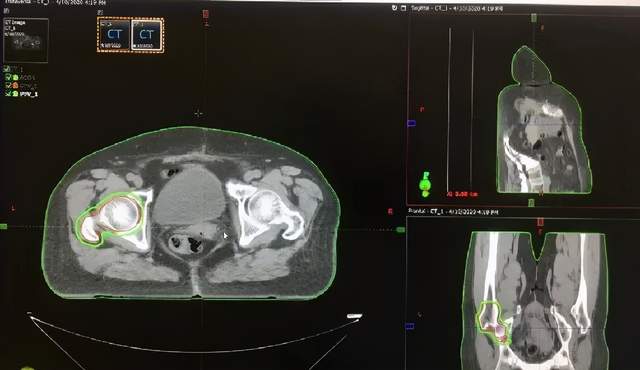

股骨头转移放疗